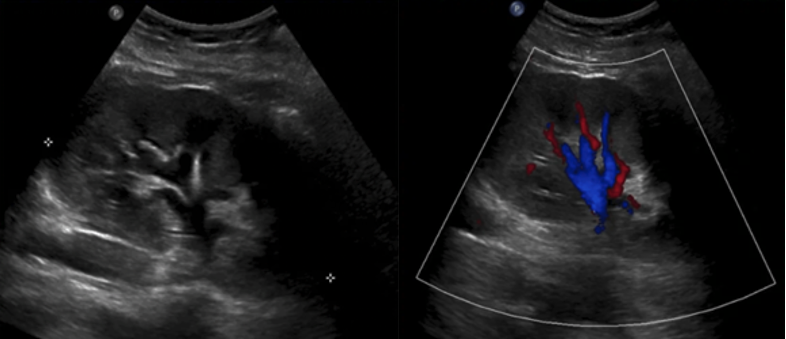

Subcostal Four Chamber

The subxiphoid 4 Chamber view can be used to assess ventricular function, particularly during emergent situations, when access to the other windows is limited.

The left ventricle is seen in the far field with the septal and lateral walls in view. The RV is seen more anteriorly.

Figure 25. Subxiphoid 4 chamber with the LV walls labeled

What is Normal

Contractility:

All visible LV walls should demonstrate symmetric inward motion and thickening, moving toward the center of the ventricle in a coordinated fashion.

Figure 26. Subxiphoid 4 chamber view with normal LV function

What is NOT Normal

Decreased global function:

The LV walls will fail to contract effectively toward the center of the cavity during systole. Wall motion appears sluggish or diminished, and the overall inward movement and thickening are reduced (figure 27).

Figure 27: Subxiphoid 4 Chamber demonstrating reduced LV systolic function. Video courtesy of Dave Kirschner